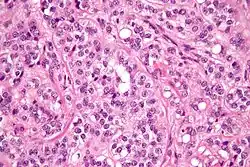

Micrograph of a Leydig cell tumour